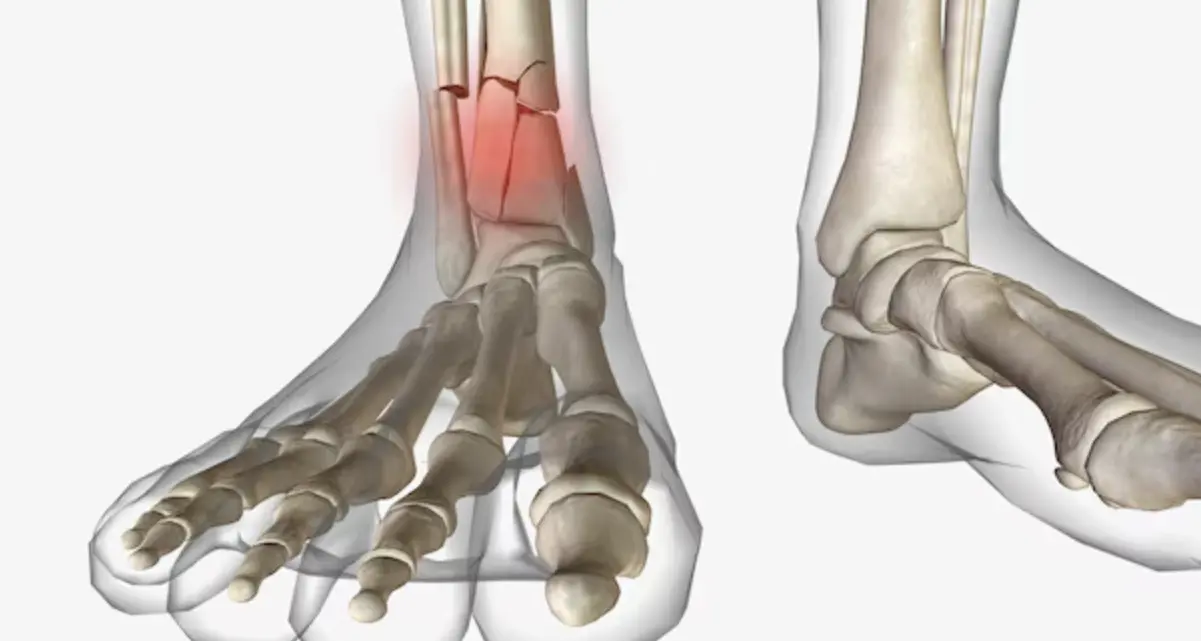

3. تاپان ئارىلىق سۆڭىكى سۇنۇش: پۇت ئىقتىدارىنىڭ دۈشمىنى

تاپان ئارىلىق سۆڭىكى (Talus) پۇت بىلەن پاقالچاقنى تۇتاشتۇرىدىغان مۇھىم بوغۇم سۆڭىكىدۇر. ئۇ پۈتۈن بەدەننىڭ ئېغىرلىقىنى كۆتۈرىدۇ. بۇ سۆڭەكنىڭ يۈزىنىڭ %60 تىن كۆپرەكى بوغۇم پەلەمپەيسى بىلەن قاپلانغان بولۇپ، مۇسكۇللار بىۋاسىتە چاپلاشمايدۇ. شۇڭلاشقا، ئۇنىڭ قانسىراش ئەھۋالى ئىنتايىن ئېغىر بولىدۇ.

- سۇنۇقتىن كېيىنكى نېكروزلىنىش نىسبىتى %70 كە يېتىشى مۇمكىن.

- بىمارلار ئادەتتە ئۇزۇن مۇددەت يەر بېسىپ ماڭالمايدۇ، بۇ تۇرمۇشقا زور قولايسىزلىق ئېلىپ كېلىدۇ.

- بوغۇم ياللۇغى كېيىنكى مەزگىلدىكى ئەڭ كۆپ كۆرۈلىدىغان ئەگەشمە كېسەللىكتۇر.

زامانىۋى تىببىي تەتقىقاتلار سۆڭەك ساقىيىشىنىڭ يېڭى ئۇسۇللىرى ئۈستىدە توختىماي ئىزدىنىۋاتىدۇ. مەسىلەن، 2024-يىلى Nature Communications ژۇرنىلىدا ئېلان قىلىنغان بىر تەتقىقاتتا كۆرسىتىلىشىچە، غول ھۈجەيرە تېخنىكىسىنى ئىشلىتىپ سۆڭەك شالاڭلىشىش ئارقىلىق كېلىپ چىققان سۇنۇقلارنى تېزلىتىش مۇمكىن ئىكەن. شۇنىڭ بىلەن بىر ۋاقىتتا، 2023-يىلى The Lancet ژۇرنىلىدا بېسىلغان ماقالىدە پاقالچاق سۆڭىكى سۇنۇشنى داۋالاشتا بىئولوگىيىلىك رېلىسنىڭ ئەنئەنىۋى پولات مىخلارغا قارىغاندا ساقىيىش سۈرئىتىنى ئاشۇرۇپ، ئەگەشمە كېسەللىكلەرنى ئازايتىدىغانلىقى ئىسپاتلانغان.